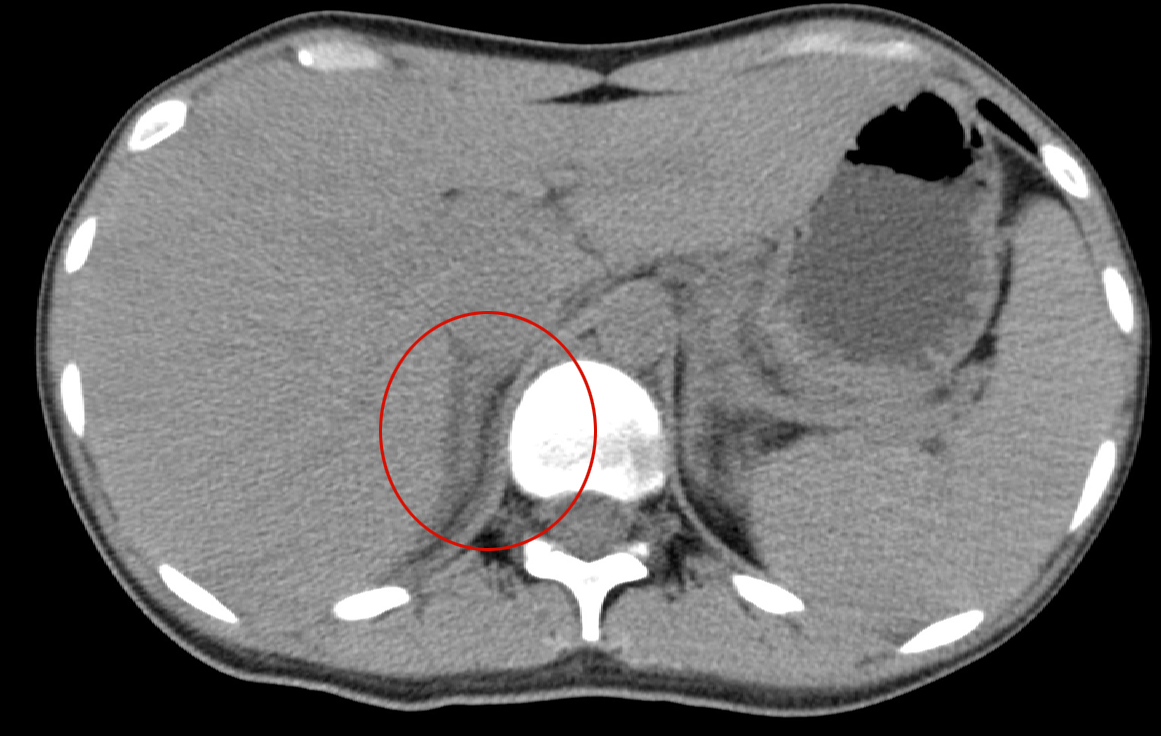

- 【KEY画像】

- 左副腎の腫大

- 左副腎の造影不良

- 脾腫